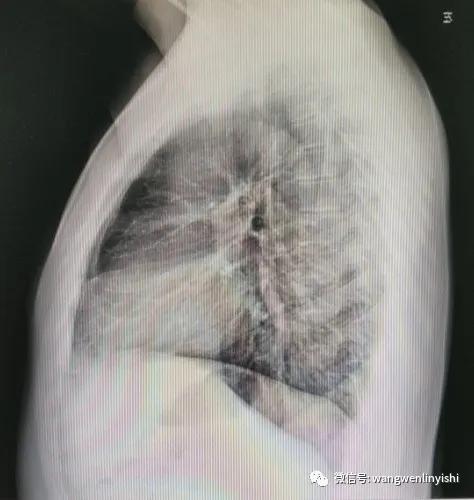

入院查体:前胸壁整体严重前突,外观呈桶状,肋间隙未增宽,无三凹征,胸围102.5CM。影像学检查提示桶状胸。患者有明确手术指征,无禁忌症,经充分术前准备,今天上午实施手术治疗。

(X线提示重度胸廓畸形)